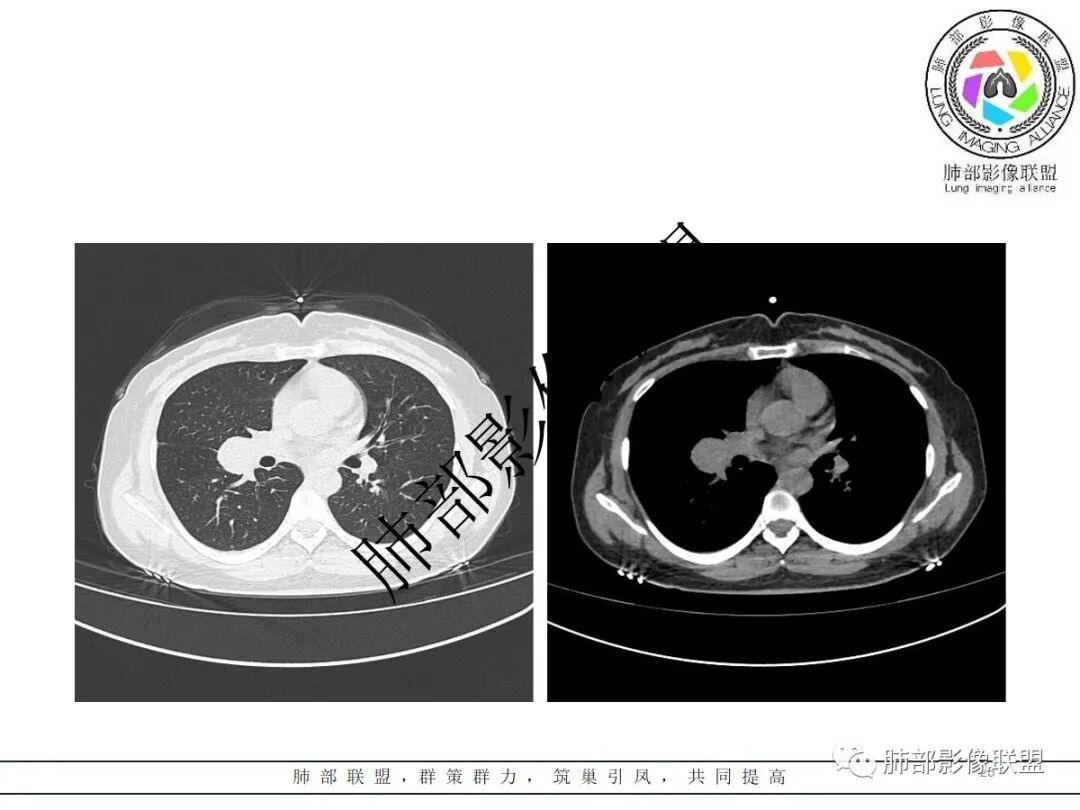

右肺门类圆形实性肿块,边缘光滑,无分叶毛刺,跨叶,推移血管,密度均匀,增强延迟强化相对明显,未见坏死及血管造影征。

右肺门区类圆形肿块,跨叶,边缘光滑,密度均匀,血管贴边,推移,延迟强化,考虑PSP,鉴别CD

2.右肺水平叶裂斜叶裂肺门交界区类椭圆形块影,表面光整,未见分叶毛刺及棘状突起,未见邻近结构牵拉。与邻近支气管无关联。

3.病灶密度均匀,未见液化坏死、钙化及脂肪低密度。轻度强化,可见纤细血管影蜿蜒穿行。右肺动脉推移变形,未见侵入或充盈缺损。

4.灶周未见磨玻璃晕或极低密度影环绕。右肺下叶背段胸膜下见微小实性密度结节影,边界清楚。

5.双肺门及纵隔未见增大淋巴结。双侧胸腔未见积液。